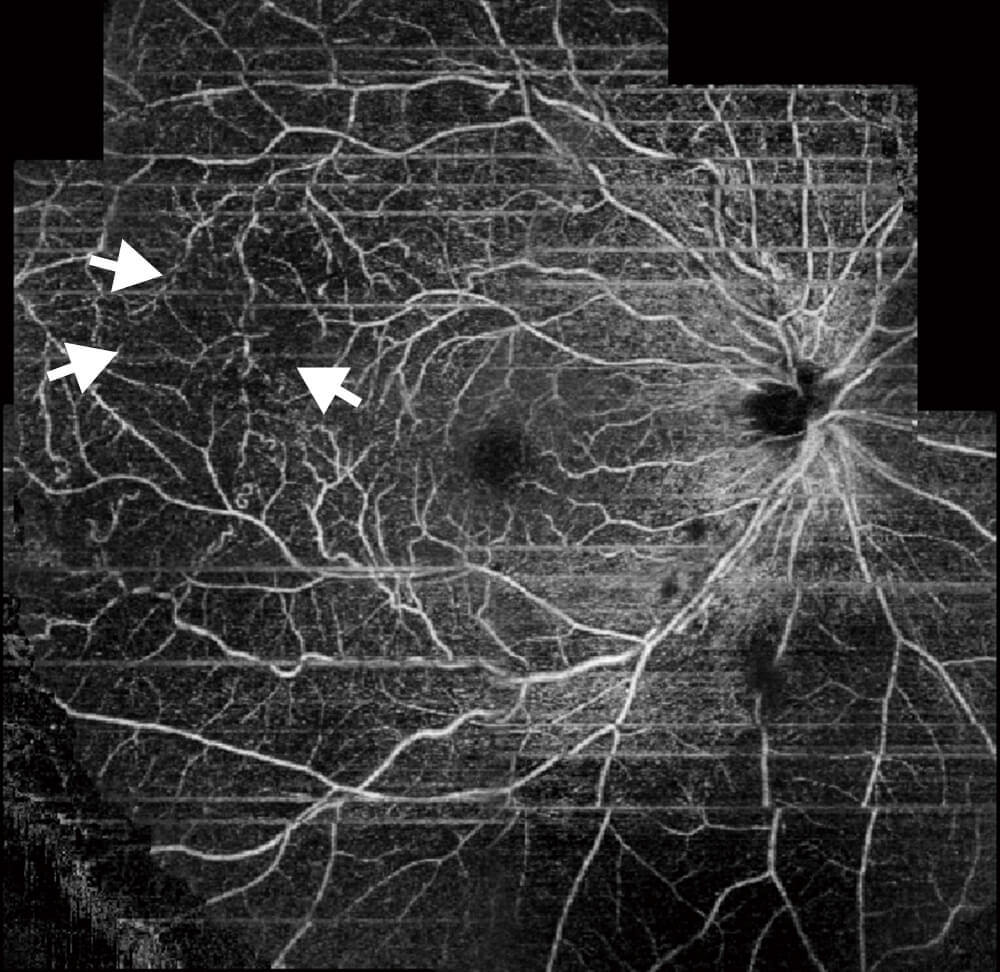

- 光干渉断層血管撮影 OCTA(OCT-Angiography)

- 光干渉断層血管撮影(OCT-Angiography)は、OCTの技術を応用した新しい検査方法です。網膜の血流形態を非侵襲(体に触れない・造影剤を必要としない)で撮影することが可能です。無灌流領域(網膜に血液が流れていない部分)の検出や新生血管(酸素不足により出来た新しい血管)の評価に有用です。

この撮影により、糖尿病網膜症、網膜静脈閉塞症等の網膜の虚血性変化を確認することができ、レーザー治療の必要性が判断できます。強い虚血性変化があれば、レーザー治療を開始します。

対象疾患:糖尿病網膜症・加齢黄斑変性・網膜静脈閉塞症 など

光干渉断層血管撮影OCTA(糖尿病網膜症)

糖尿病網膜症による血管吻合と無血管野が確認できます。これによりレーザー治療の必要性を判断します。